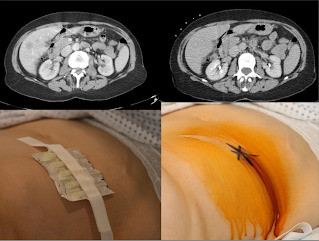

Biopsia percutanata se defineste drept insertia unui pistol de biopsie intr-o leziune suspecta sau un organ cu scopul obtinerii de tesut sau celule pentru diagnostic. Introducerea acului se face prin piele, de unde si denumirea de "biopsie percutanata"(Lat. per = prin; cutaneous = piele). Aceasta procedura se face sub ghidaj imagistic.

Procedura se efectueaza sub ghidaj imagistic precum ecografie, CT, sau RMN. Tehnica imagistica adoptata depinde de tipul si localizarea leziunii, complianta pacientului, disponibiliatea tehnicii si preferintele operatorului.

• Biopsia presupune folosirea unui ac gol cu un mecanism de taiere si captare ce permite extragerea unei piese de tesut pentru evaluarea histologica. Succesul tehnic al biopsiei percutanate se defineste ca procurarea de material suficient pentru stabilirea diagnosticului si ghidarea deciziilor terapeutice.

Comparativ cu biopsia intraoperatorie sau excizionala, biopsia percutanata sub ghidaj imagistic poate fi propusa ca interventie in regim ambulator in majoritatea cazurilor. Procedura se realizeaza sub anestezie.